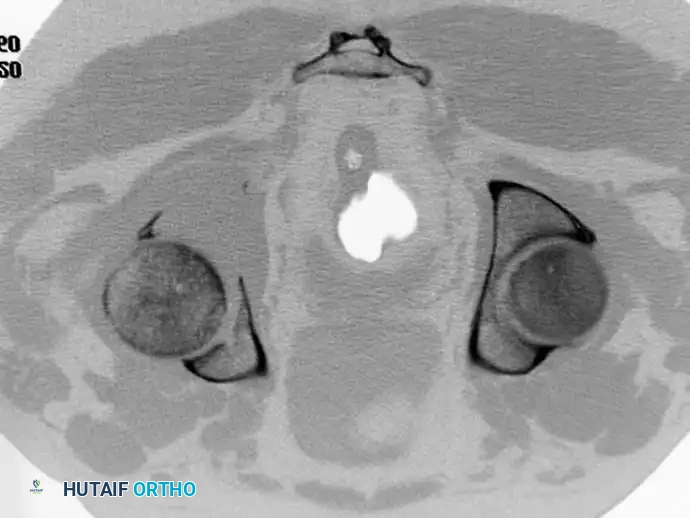

Fig. 22-23: (A, B) Radiograph and CT of a 66-year-old man with metastatic lung cancer destroying the right acetabular posterior column and wall. Preoperative embolization was performed to minimize blood loss. (C) Intraoperative view after curettage. Guidewires were placed from the defect to the posterior ilium and anterior iliac crest. Cannulated screws were placed over the wires to support the cement mantle. (D) An acetabular cage was placed, and the defect was filled with PMMA as the cup was cemented. (E) Postoperative radiograph demonstrating a stable construct.